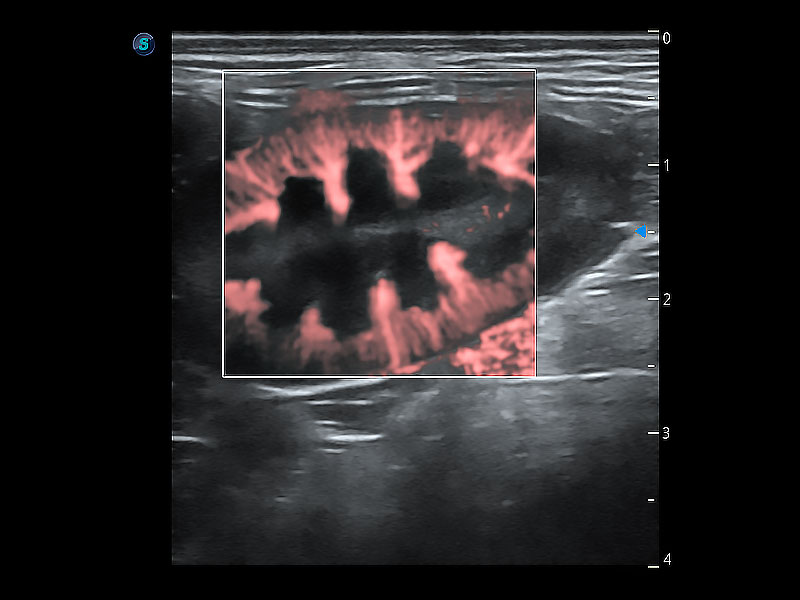

了若指掌 腹部/淺表解決方案

高性能和先進(jìn)的臨床應(yīng)用工具可以為動物醫(yī)生提供臨床信心。ProPet 80 搭載了先進(jìn)的腹部和淺表應(yīng)用工具,幫助醫(yī)生在日常臨床實踐中發(fā)揮前所未有的作用。

• Micro F 顯微血流成像

極大提升超低速微細(xì)血流的檢出能力,同時更精準(zhǔn)地濾除軟組織和超聲信號,為獸用醫(yī)生提供以往無法通過常規(guī)血流獲得的疾病診斷信息。

(犬)腸道

(犬)腎臟顯微血流